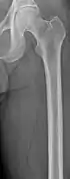

The diagnostic examination of a person with suspected multiple myeloma typically includes a skeletal survey. This is a series of X-rays of the skull, axial skeleton, and proximal long bones. Myeloma activity sometimes appears as "lytic lesions" (with local disappearance of normal bone due to resorption) or as "punched-out lesions" on the skull X-ray ("raindrop skull"). Lesions may also be sclerotic, which is seen as radiodense.[70] Overall, the radiodensity of myeloma is between −30 and 120 Hounsfield units (HU).[71] Magnetic resonance imaging is more sensitive than simple X-rays in the detection of lytic lesions, and may supersede a skeletal survey, especially when vertebral disease is suspected. Occasionally, a CT scan is performed to measure the size of soft-tissue plasmacytomas. Bone scans are typically not of any additional value in the workup of people with myeloma (no new bone formation; lytic lesions not well visualized on bone scan).

Multiple myeloma in the upper arm

Femur with multiple myeloma lesions